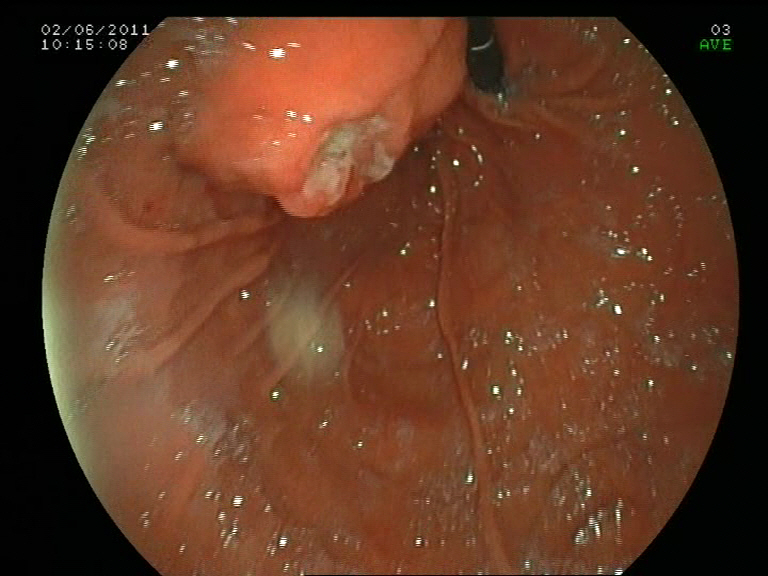

Los tumores GIST (gastrointestinal stromal tumors) son una causa común de lesiones subepieteliales del tracto gastrointestinal. Se consideran lesiones premalignas. De hecho, hasta el 10-30 % de éstas lo son en el momento del diagnóstico. La localización mas común es el estómago. Anteriormente muchas de estas lesiones se catalogaban como leiomiomas gástricos. Su origen se encuentra en las células intersticiales de Cajal y de forma típica, con tinciones de inmunohistoquímica, expresan el marcador CD-117 (también conocido como C-Kit protein; receptor de membrana con actividad para la enzima tirosin-kinasa). Desde el punto de vista endosonográfico se originan en la 4ª capa (muscularis propria), siendo generalmente asintomáticos o manifestándose como HDA (melenas o hematemesis si se ulceran en su vértice, como el caso que se presenta). Suelen ser homogéneos en su ecoestructura. Cuando superan los 3 cm, el borde extraluminal es irregular, aparecen espacios quísticos en su interior o focos hiperecogénicos o bien hay adenopatias perigástricas, existe un mayor riesgo de que sean maligno. El diagnóstico se suele realizar por USE-PAAF, o bien como en este caso, tomando biopsias endoscópicas de la zona ulcerada. La positividad para el C-Kit y el índice mitótico establecen el diagnóstico y su carácter maligno o no. El tratamiento en la mayoría de los casos, cuando son de carácter benigno o localizados, es quirúrgico solamente. Cunado son menores de 2 cm, se confirman que dependen exclusivamente de la 4ª capa y sin afectación local o a distancia, pueden tratarse con la colocación de un lazo (endoloop) y su resección con asa. En casos de malignidad asociado a metástasis ganglionares o a distancia (p.e hepáticas) se basa en la quimioterapia selectiva con inhibidores selectivos de la tirosin-kinasa: imatinib o sunitinib.